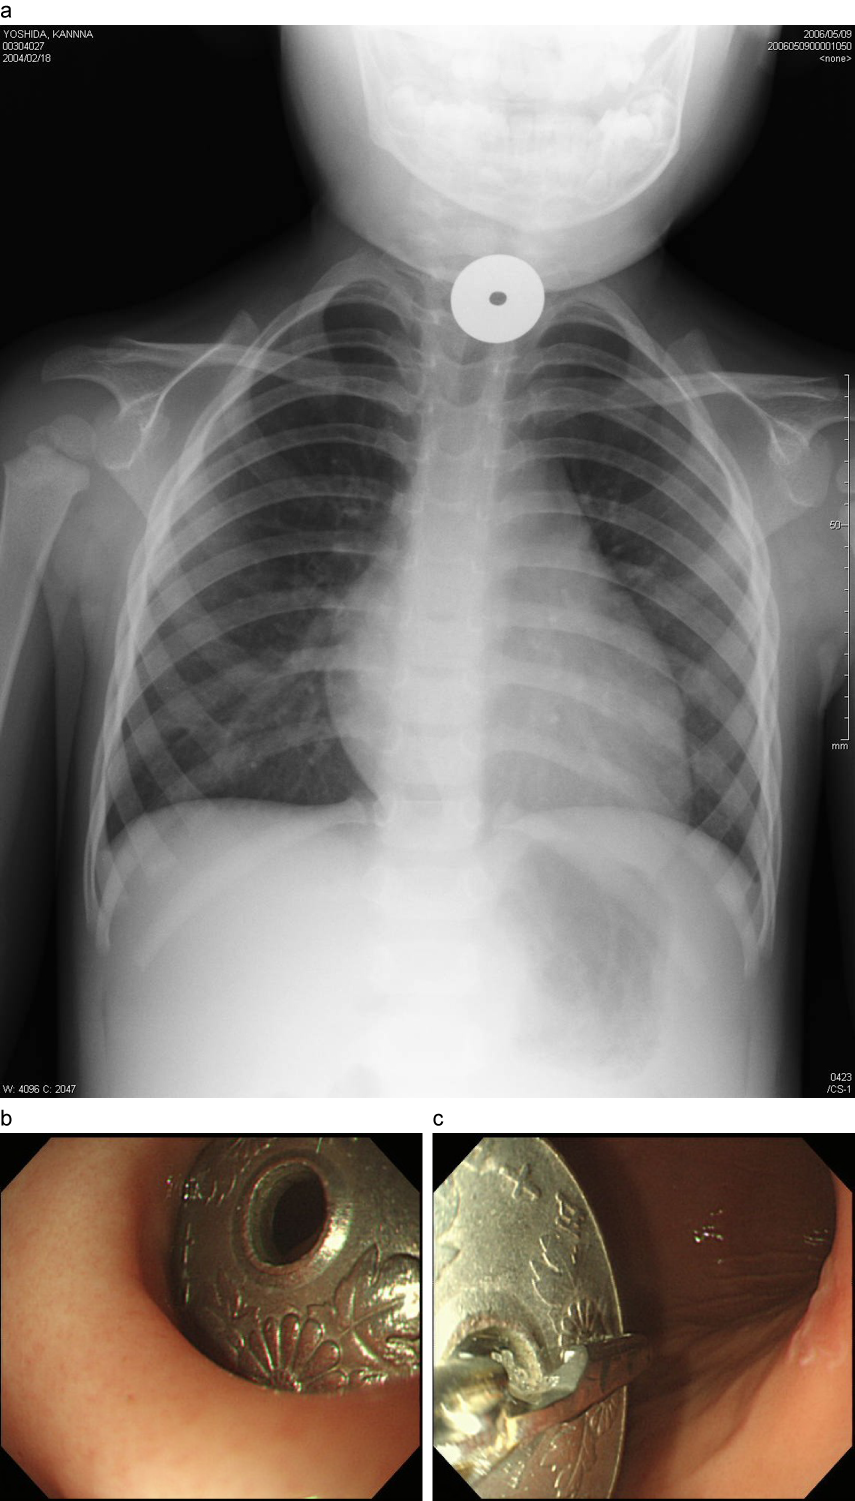

食道異物(50円硬貨)例

a:食道第1狭窄部に異物(50円硬貨)を認める。

b:摘出時には、異物は幽門輪にはさまれるような形で存在していた。c:内視鏡下に把持鉗子にて摘出した。